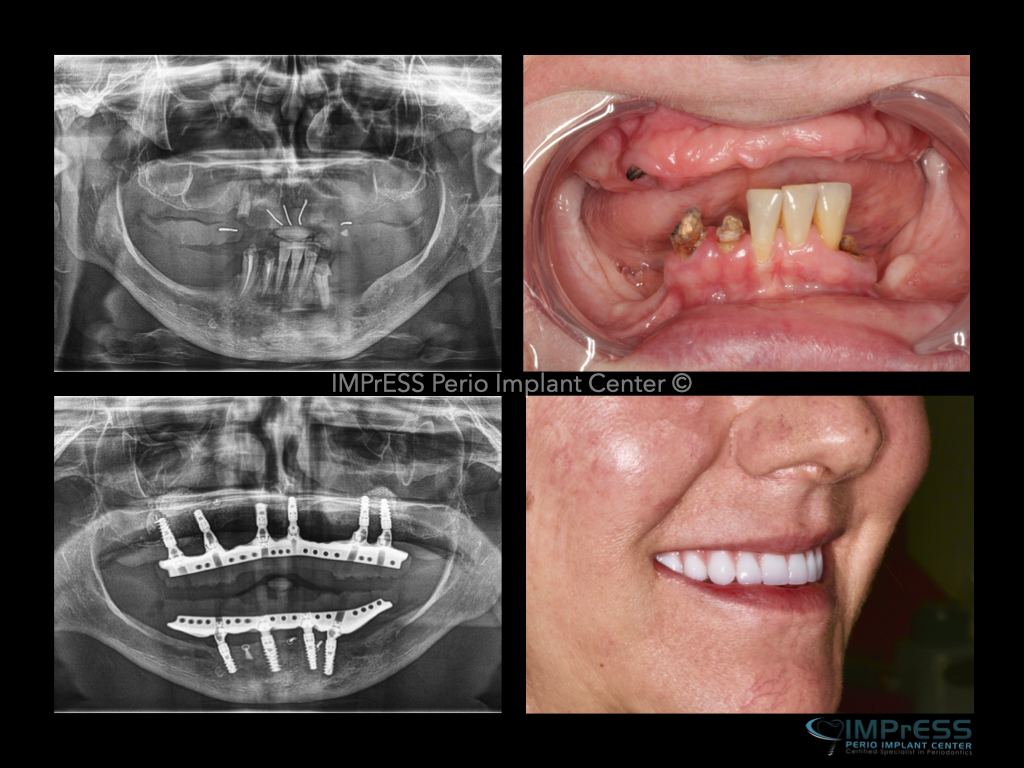

Before & Afters of Dental Implant Patients

Complete Dental Implant Cases Gallery

Dental implant treatment is sometimes a team effort between your periodontist and a restorative dentist.  Dr. Noroozi  at IMPrESS Perio Implant Center located in Burnaby BC performs the actual implant surgery, initial tooth extractions, and bone and gum grafting if necessary.  The restorative dentist (your dentist) or our specialists (if you do not have a dentist) will fit and make the permanent prosthesis. Your dentist or our specialists will also make any temporary prosthesis needed during the implant process.

General Disclaimer: The results in the photographs are examples only and do not imply any certainty of the result of a procedure, and all outcomes are subject to the circumstances of the individual patient.